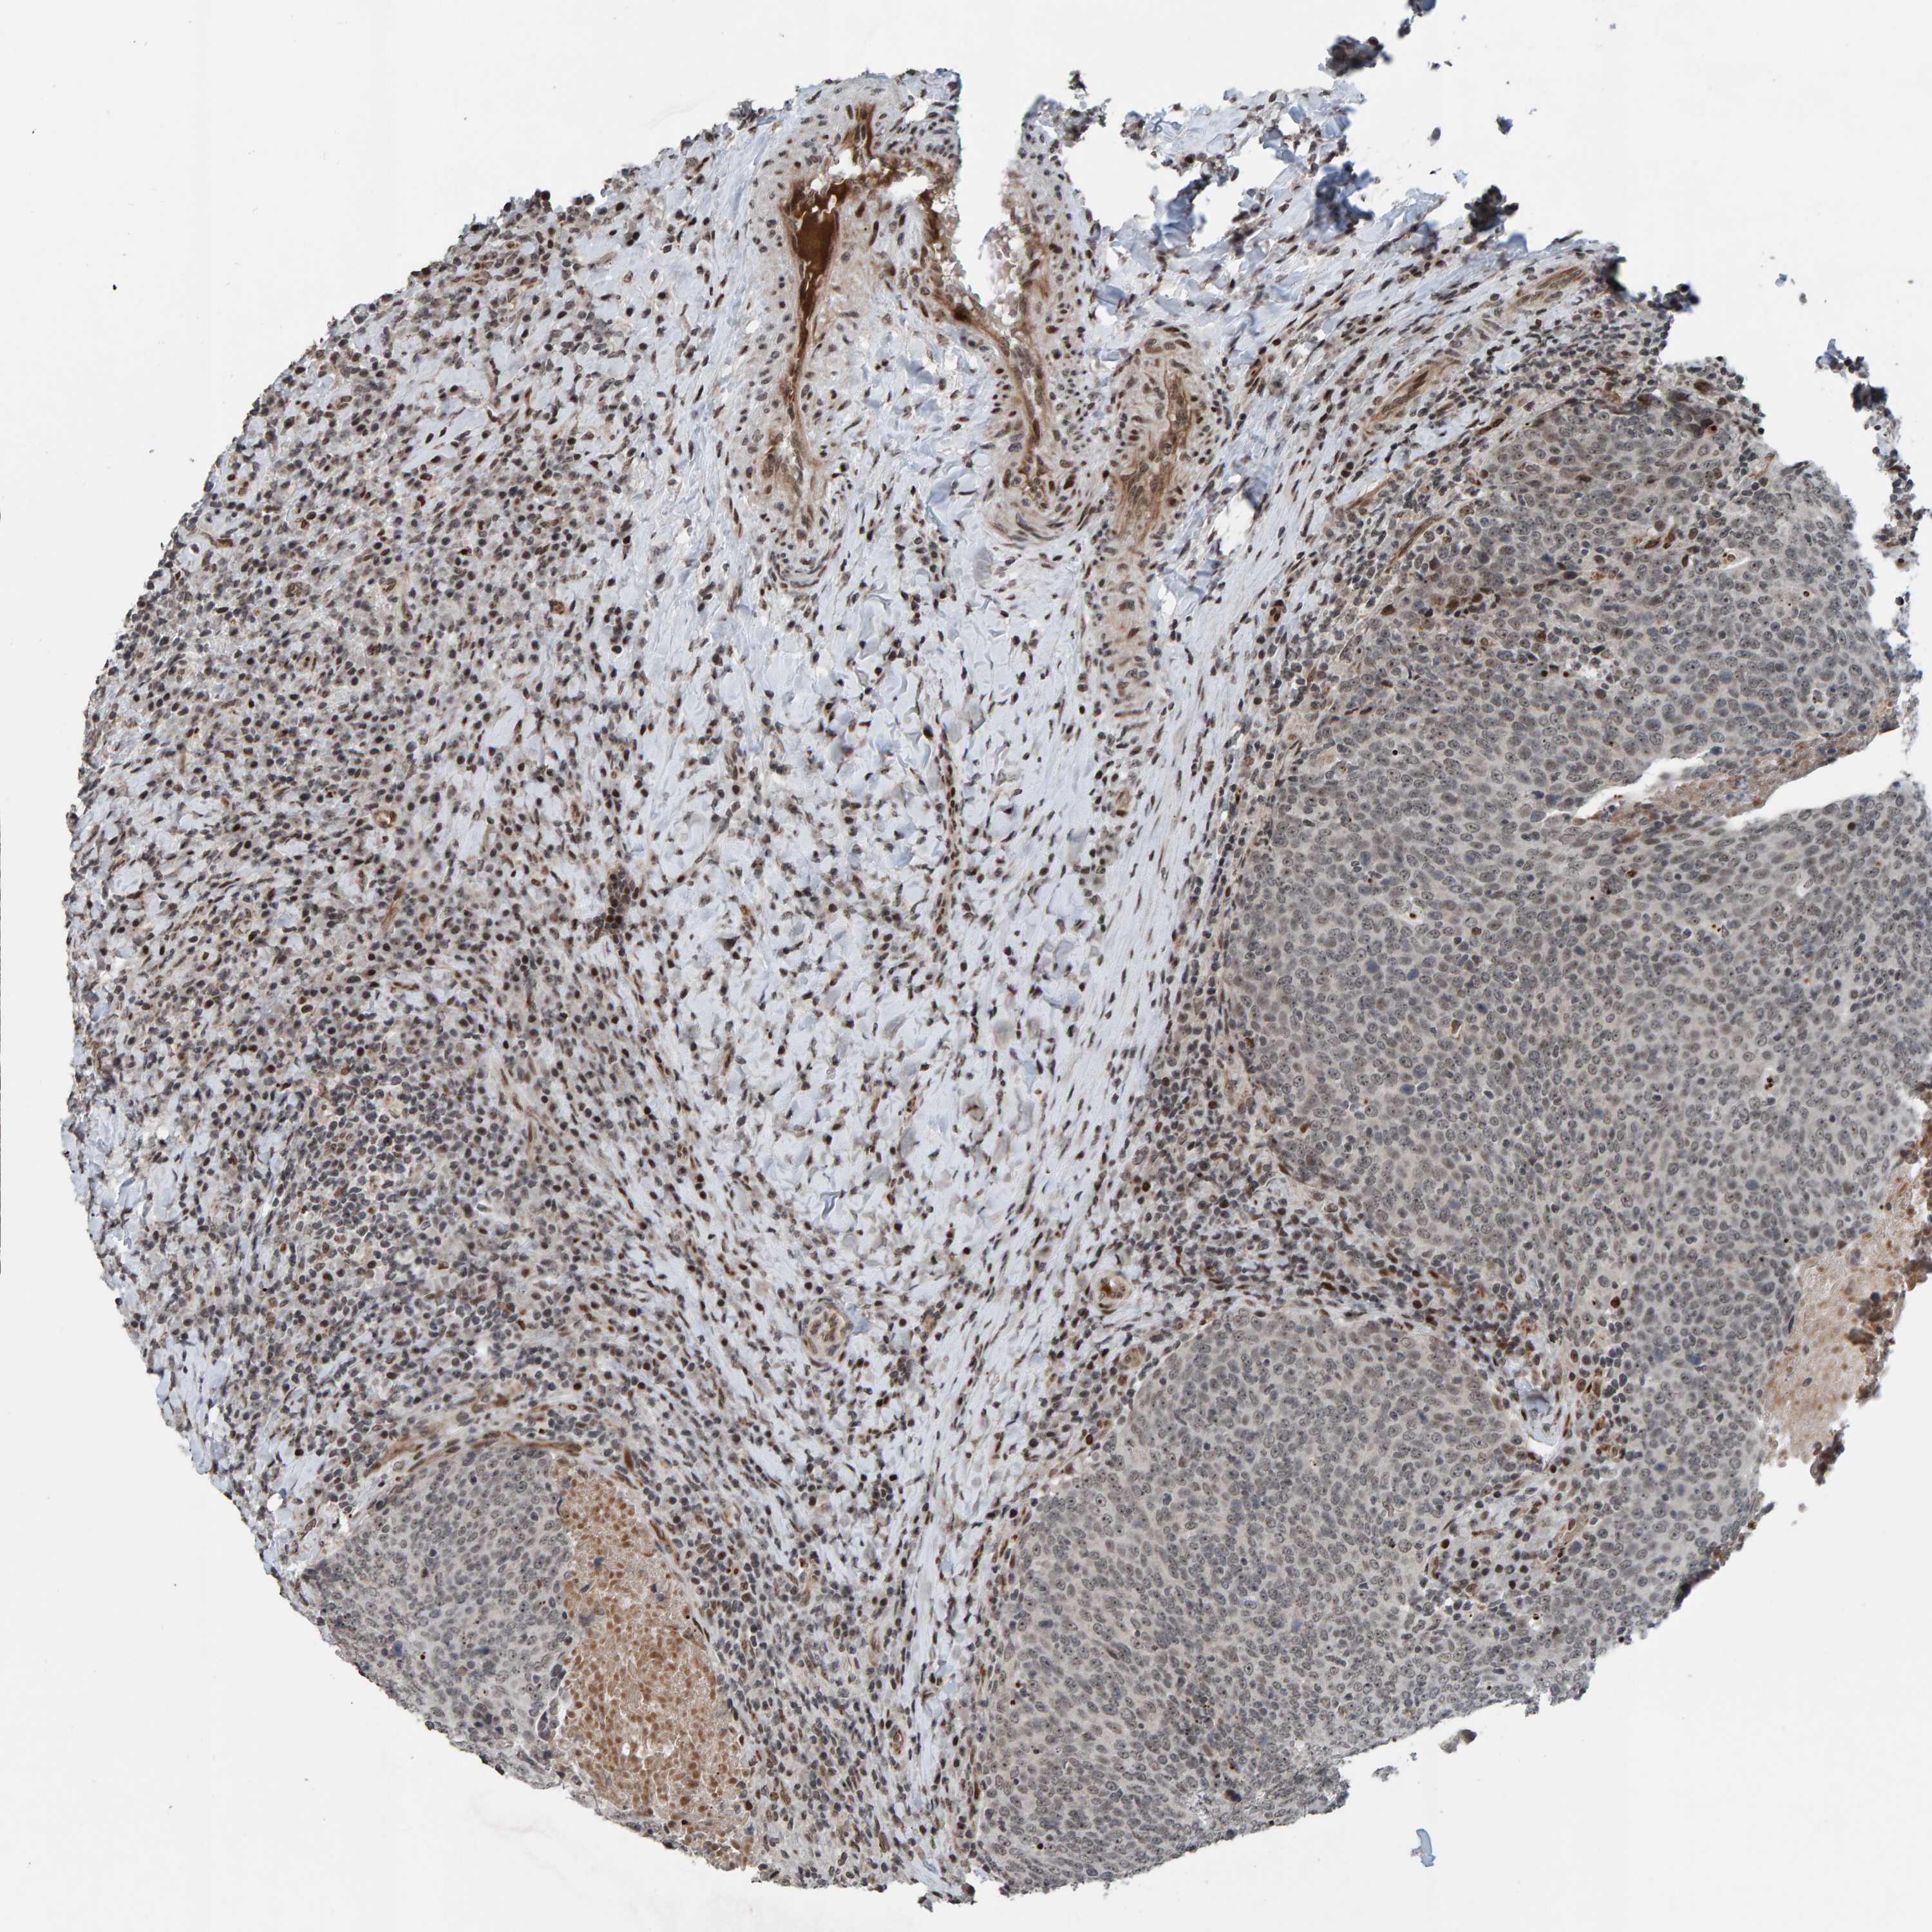

HEAD AND NECK CANCER - Protein expressioni

A mouse-over function shows sample information and annotation data. Click on an image to view it in a full screen mode. Samples can be filtered based on level of antibody staining by selecting one or several of the following categories: high, medium, low and not detected. The assay and annotation is described here.

Antibody stainingi

Antibody staining in the annotated cell types in the current human tissue is reported as not detected, low, medium, or high, based on conventional immunohistochemistry profiling in selected tissues. This score is based on the combination of the staining intensity and fraction of stained cells.

Each image is clickable and will lead to virtual microscopy that enables deeper exploration of all samples and also displays staining intensity scores, fraction scores and subcellular localization as well as patient and tissue information for each sample.

Antibody HPA023128

Antibody HPA023526

Staining

High

Medium

Low

Not detected

Intensity

Strong

Moderate

Weak

Negative

Quantity

>75%

75%-25%

<25%

None

Location

Nuclear

Cytoplasmic/membranous

Cytoplasmic/membranous,nuclear

Squamous cell carcinoma, NOS

Squamous cell carcinoma, metastatic, NOS

Adenocarcinoma, NOS